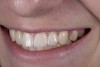

(1.) Initial presentation. Note midline shift to right, missing right lateral incisor, and diminutive left lateral incisor in crossbite.

Figure 1

A 14-year-old patient presented to the office with his mother (Figure 1). His chief complaint involved the large spaces between the teeth created by his missing right maxillary lateral incisor and his small left maxillary lateral incisor. He desired to replace the missing tooth with an implant and create a beautiful smile. Upon examination, he was found to have a class I canine and molar relationship, but because he had a tooth size/arch size discrepancy and space distal to the right central incisor, the remaining incisors had drifted to the right. The left maxillary lateral incisor was peg-shaped and in a cross bite position. Studies have shown a clear association between congenitally missing teeth and reduced tooth size.59-62 Because he was only 14 years old at the time and could not have implants placed until the cessation of growth (somewhere in the vicinity of 22 years old), he was sent to the orthodontist for alignment of the teeth.16,17 After 2 years of orthodontics, the appliances were removed, and his tooth coloration was improved using carbamide peroxide bleaching (Figure 2). Because some form of provisional needed to be placed until he was finished growing, a double-wing metal resin-bonded bridge was chosen. As discussed earlier, this is the ideal transitional prosthesis for patients that have congenitally missing maxillary lateral incisors. The benefits of this type of prosthesis include its ability to be removed and rebonded during the surgical phase of treatment and its ability to retain the roots in their proper position after orthodontic treatment.16 The final plan for the patient was to increase the width of the central and the maxillary left lateral incisor, utilizing porcelain laminate veneers to achieve the appropriate width/length ratio of 80%. A wax-up was created to idealize tooth size, a putty matrix was made from the wax-up to facilitate bonding of the incisors, and a non-precious, double-wing metal resin-bonded bridge was fabricated for lateral incisor replacement. Once the teeth were bonded to ideal size, the “Maryland Bridge” was fabricated from a polyvinyl arch impression with the newly bonded teeth (Figure 3). The metal frame was cast from a non-precious alloy to allow for fabrication of a very thin frame and to create a better surface for bonding. After sandblasting the internal aspect of the frame with CoJet™ silica (3M ESPE), accomplishing salinization, and executing cementation with a dual-cure resin cement, a fairly good adhesion to the frame was anticipated.29 The enamel surface was etched with phosphoric acid for 30 seconds, the primer (Single Bond Plus, 3M ESPE) was applied to both the internal surface of the sandblasted framework and the etched enamel, and the bridge was cemented with RelyX™ ARC (3M Espe) dual-cured resin cement (Figure 4 and Figure 5).